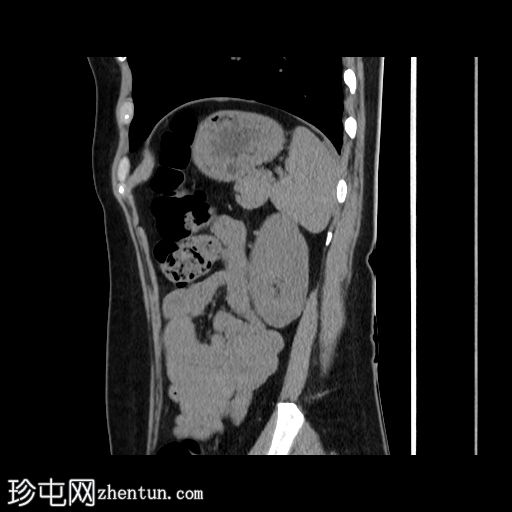

8.jpg

延迟

矢状面

在轴向、冠状面和矢状面上均可见肝5/6段病变。动脉期可见周围结节状强化,门静脉期可见进行性向心性充盈,延迟期亦持续存在。这些表现为肝血管瘤的特征性表现。

然而,目前的CT扫描显示动脉期呈周围结节性强化,门静脉期呈进行性向心性充盈,且延迟成像后仍持续存在。这些特征是肝血管瘤的特征。未发现其他肝脏病变。